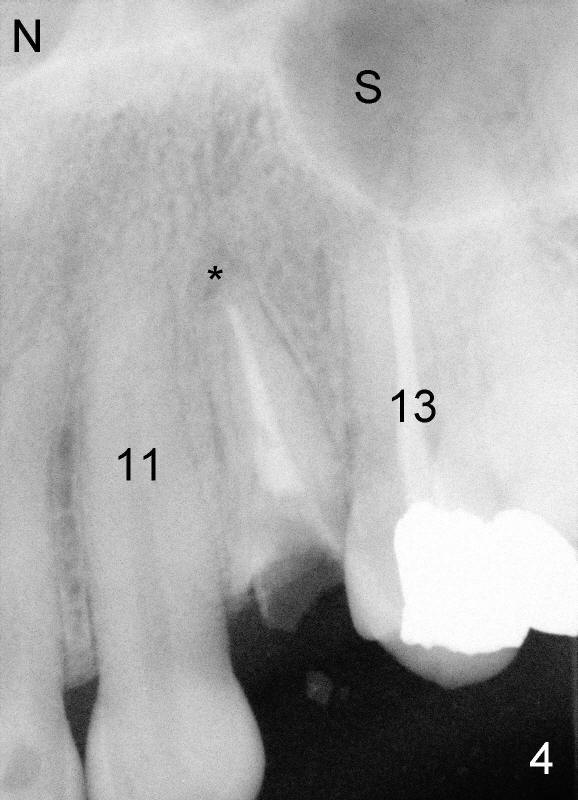

The second patient who is going to have an immediate implant in the upper bicuspid region is a 41-year-old lady. She is extremely scared of dental treatment. The second challenge is a periapical lesion associated with residual roots (Fig.1,2,4, as compared to freshly fractured tooth in the first case).

After tooth extraction, the osteotomy is initiated in the palatal socket (compare Fig.6,7 (CBCT, not the same case) with a pilot drill (pink outline). The osteotomy is enlarged by a series of reamers until the apical diameter (3.5 mm, Fig.8) of the prospective tapered implant (5x20 mm, Fig.9 I). The socket is obliterated by the tapered implant (Fig.9) with simultaneously achieving primary stability. This looks less over engineering than the first case.